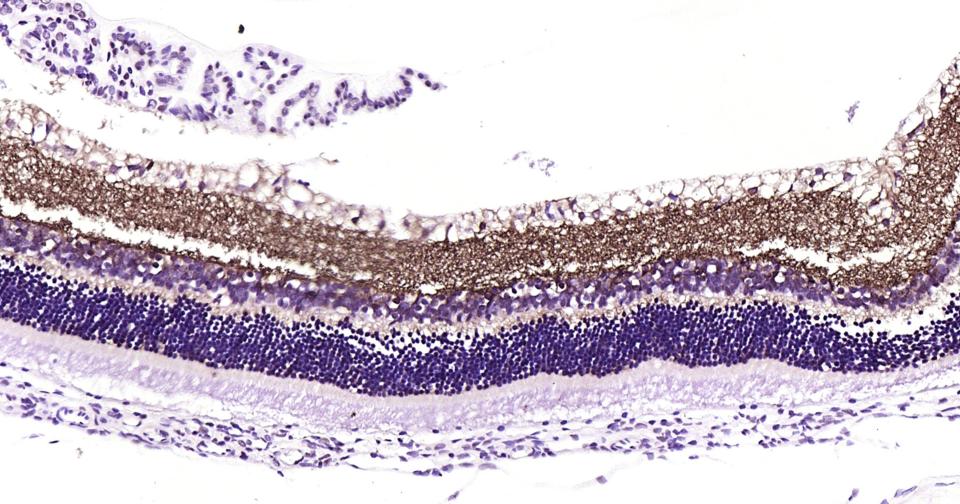

Paraformaldehyde-fixed, paraffin embedded Rat Eye; Antigen retrieval by boiling in sodium citrate buffer (pH6.0) for 15 min; Antibody incubation with GAT1?Monoclonal Antibody, Unconjugated(bsm-61879R) at 1:200 overnight at 4°C, followed by conjugation to the bs-0295G-HRP and DAB (C-0010) staining.